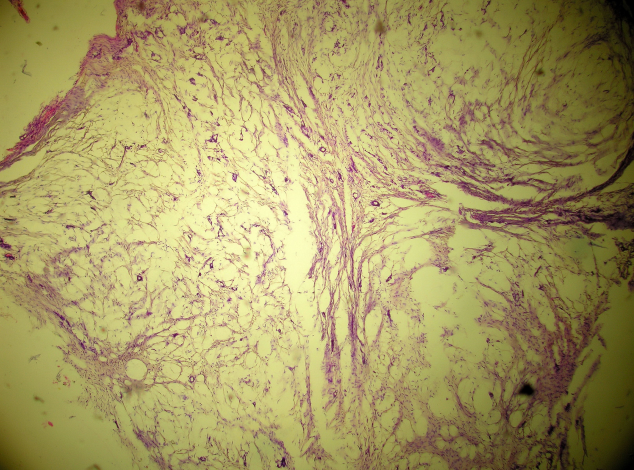

Figure 1. Histopathology of mass from ascending colon.

Poorly differentiated mucinous adenocarcinoma.